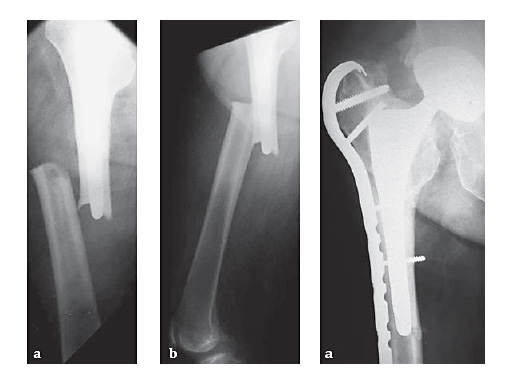

An additional important indication is periprosthetic fracture about the femoral component of a total hip arthroplasty. The trochanteric fixation of the plate (both hook and screws) affords improved proximal fixation, in many cases limiting the need for circlage wires and screws angled around the stem. Compression of primary fracture planes remains desirable in the periprosthetic setting, but is often not possible and does not limit the utility of the plate in this clinical setting. The Plate is available in lengths of 133385 mm, or 216 holes.

83-year-old maletrapped under tree he had cut downIDDM, HTN, CAD, etcJehovahs witnesson Plavix

Case provided by Keith Mayo, Tacoma, USA